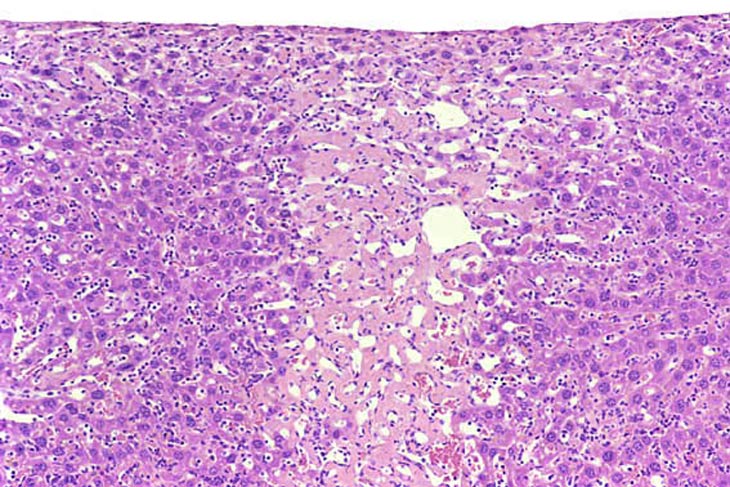

Microgranulomas consisting of mononuclear inflammatory cells and associated with hepatocyte necrosis are commonly seen in mouse liver.

Granuloma in the liver of a B6C3F1 mouse.